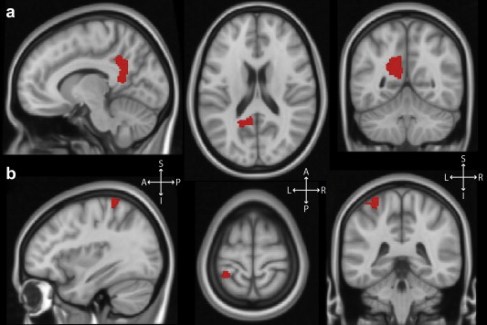

Musical hallucinations February 14, 2014brain, brain scans, brain science A report on a paper recently published in Cortex. BrainCognitionCognitive neuroscienceCognitive sciencehallucinationmusicneurophenomenologyneuroscienceOliver Sacksphantom musicShare this: Share on X (Opens in new window) X Share on Facebook (Opens in new window) Facebook Print (Opens in new window) Print Email a link to a friend (Opens in new window) Email More Share on Reddit (Opens in new window) Reddit Like Loading... Related